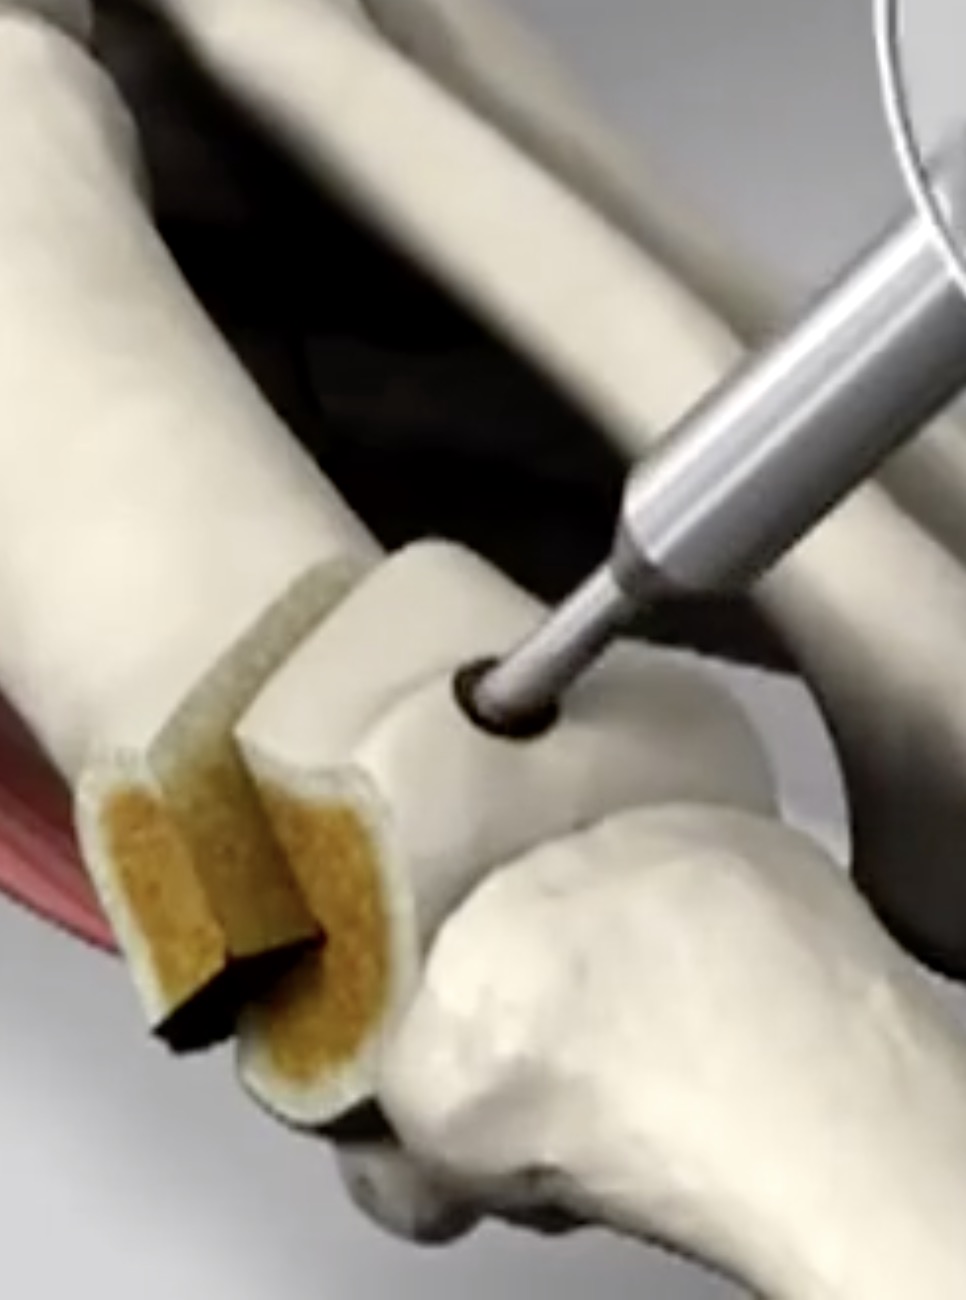

- 布骨医学科普:做完关节置换术后可以运动吗?这里有你要的答案! 布骨康复医疗中心 ,2021-04-12

- 很多做过膝关节置换术的患者都有这样的疑问,我术后可以正常走路吗?可以运动吗?走多少路合适呢?走路或者运动会不会影响我假体的寿命呢?今天给大家从业内顶级期刊《Journal of Bone & Joint Surgery-American Volume》说说膝关节置换术后的患者朋友们经常遇到的一些问题.....